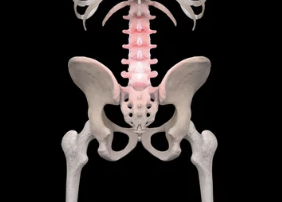

대퇴골두 무혈성 괴사

대퇴골두 무혈성 괴사는 대퇴골두에 혈액 공급이 차단되어 뼈 조직이 죽는 질환입니다. 괴사된 뼈는 점차 무너져 내리고, 이로 인해 고관절 통증이 발생합니다.